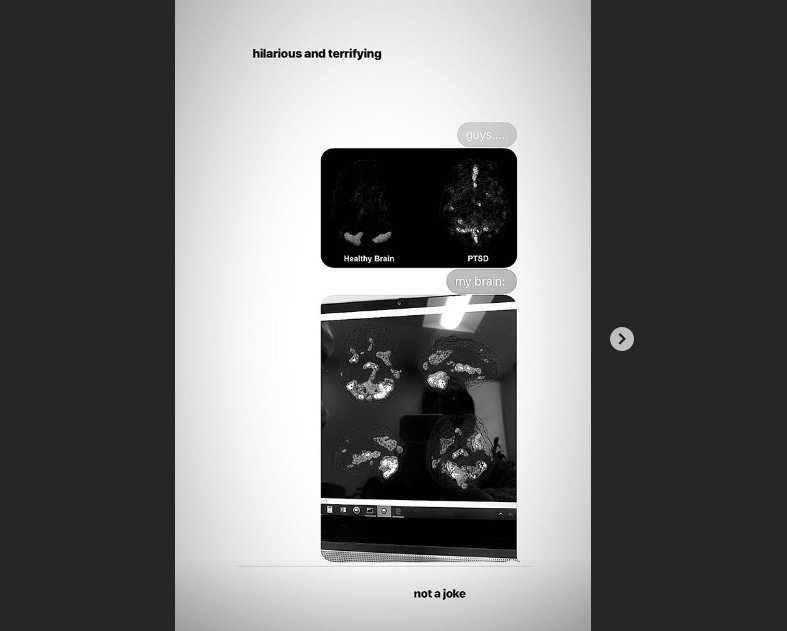

Ariana Grande soffre di un disturbo post traumatico da stress. La cantante di "Thank U, Next" è stata colta da questa malattia a seguito dell'attentato del 2017 durante un suo concerto alla Manchester Arena. Da quel giorno Ariana soffre di insonnia, depressione e ansia.

Ha parlato più volte dei suoi disturbi e ora ha mostrato ai suoi fan anche le conseguenze anatomiche del problema. La cantante ha, infatti, postato in una story su Instagram una foto del suo cervello "malato", confrontandola con la scansione di un cervello sano. "Non è uno scherzo", ha scritto Ariana. Ecco l'immagine.

Nella foto si vede subito la differenza, anche se non siamo medici. Un cervello normale non mostra zone più chiare. Quello affetto da PTSD, invece, sì.